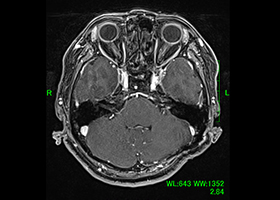

[画像所見]

頭部MRI -

頭部造影三次元CT

左後下小脳動脈が左舌咽神経を圧迫していたために左咽頭部を中心に激しい痛みが生じていました。